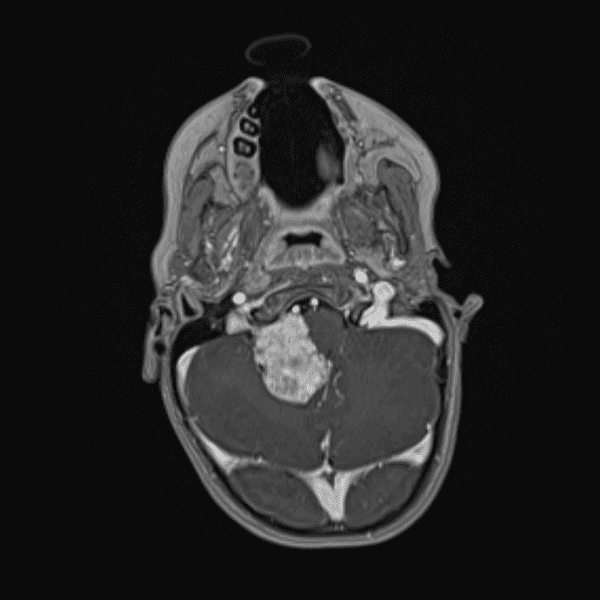

Classic Cases